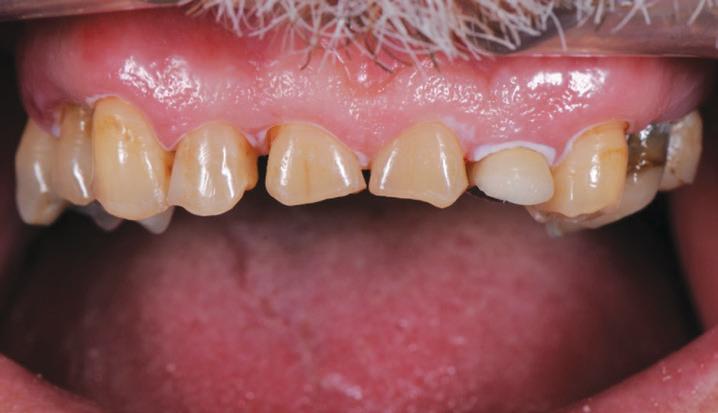

This gentleman presented with pain in his upper left quadrant. He had not been to a Dentist for many years and his dental experience had primarily been to have problematic teeth extracted (Fig. 1). As a result, he no longer had any of his molar teeth, but had been functioning well with his remaining premolar occlusion.

After his examination appointment, it was clear that the two premolars in the upper left quadrant had significant apical pathology and could not be predictably treated. His remaining dentition showed generalised attrition subsequent to dental erosion from gastric reflux, and his lower anteriors showed recession and some loss of periodontal support (Figs. 2, 3).

BEFORE